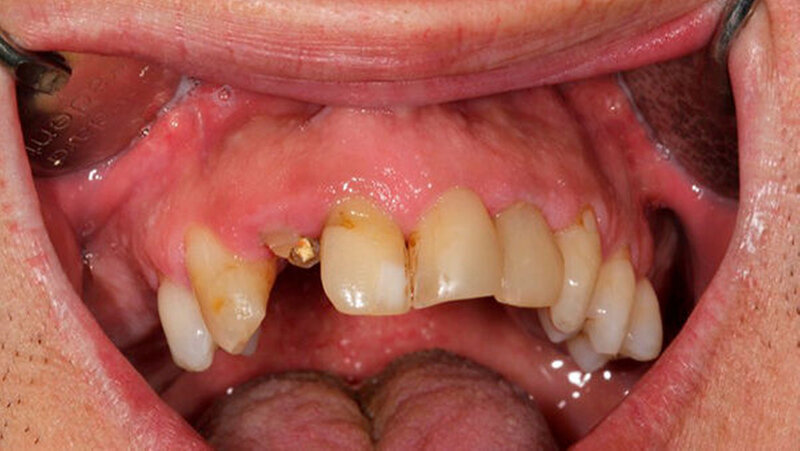

Oralchirurg Marcus Stoetzer arbeitete drei Monate lang im Feldlager der Bundeswehr in Mazar e Sharif - insgesamt behandelte er in Afghanistan 298 Soldaten. Die Bilder zeigen, aus welchem Grund sie zu ihm kamen.